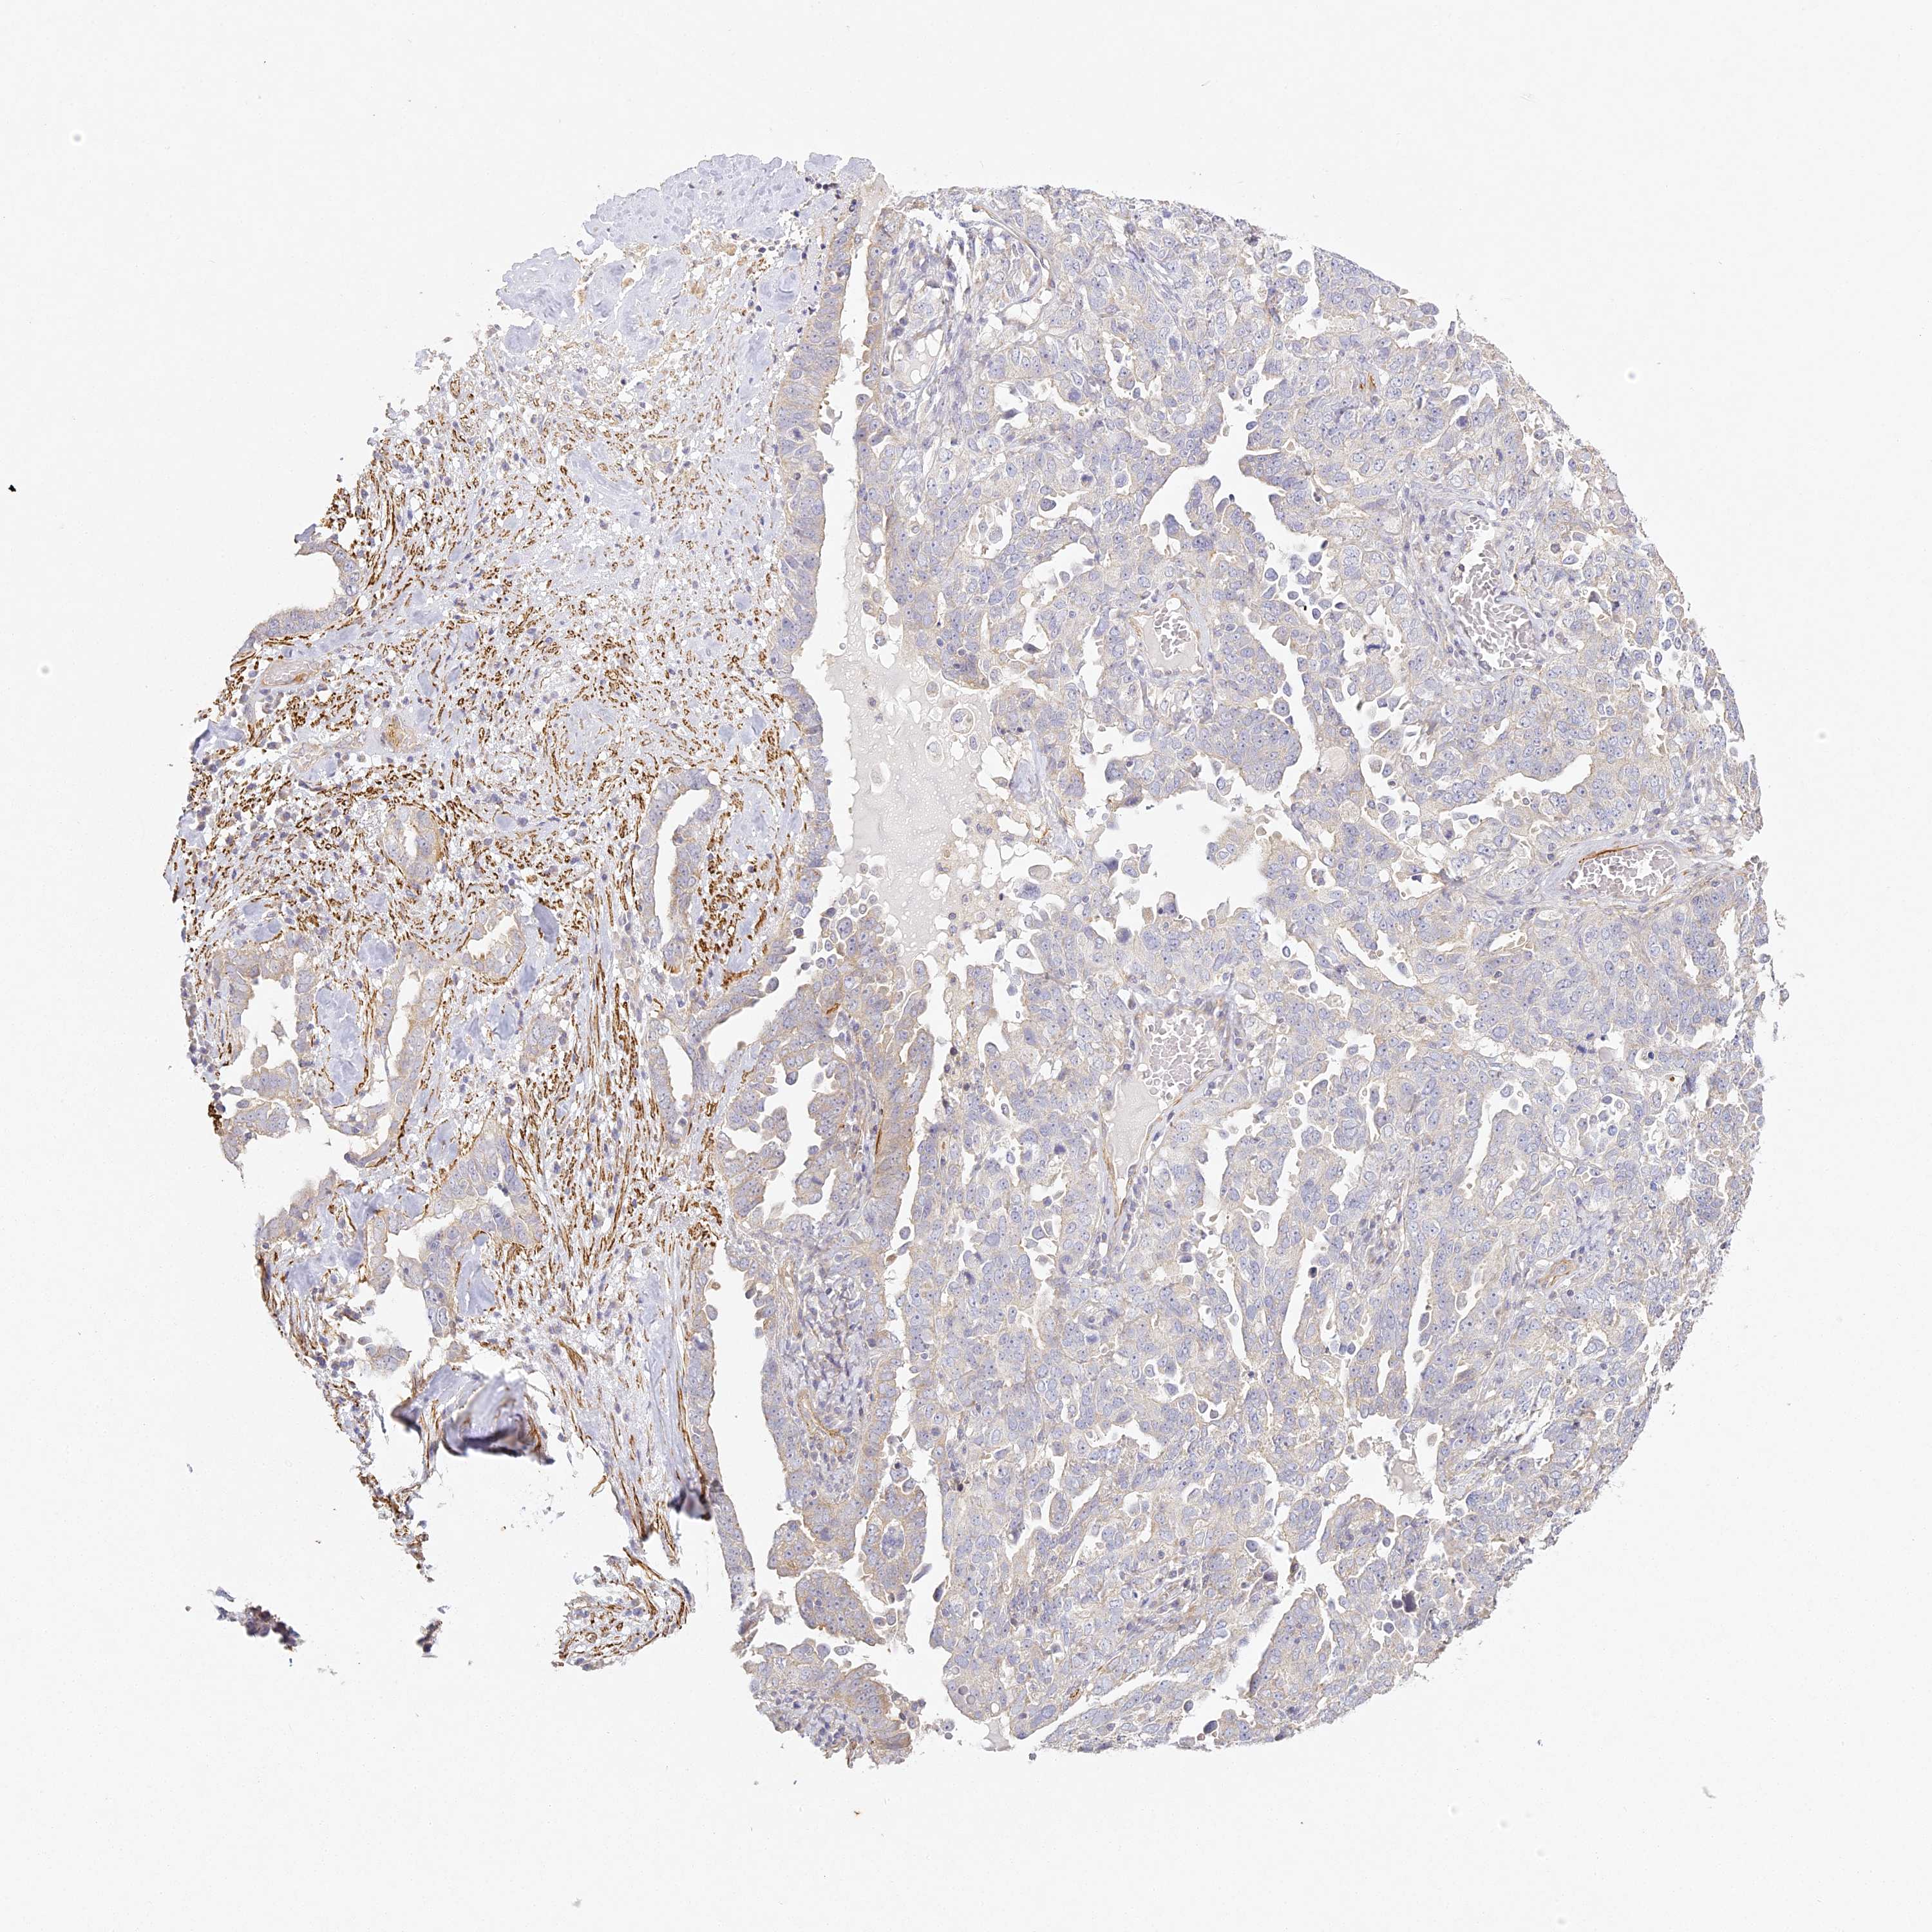

OVARIAN CANCER - Protein expressioni

A mouse-over function shows sample information and annotation data. Click on an image to view it in a full screen mode. Samples can be filtered based on level of antibody staining by selecting one or several of the following categories: high, medium, low and not detected. The assay and annotation is described here.

Note that samples used for immunohistochemistry by the Human Protein Atlas do not correspond to samples in the TCGA dataset.

Antibody stainingi

Antibody staining in the annotated cell types in the current human tissue is reported as not detected, low, medium, or high, based on conventional immunohistochemistry profiling in selected tissues. This score is based on the combination of the staining intensity and fraction of stained cells.

Each image is clickable and will lead to virtual microscopy that enables deeper exploration of all samples and also displays staining intensity scores, fraction scores and subcellular localization as well as patient and tissue information for each sample.

Antibody HPA035900

Antibody HPA035901

Carcinoma, NOS